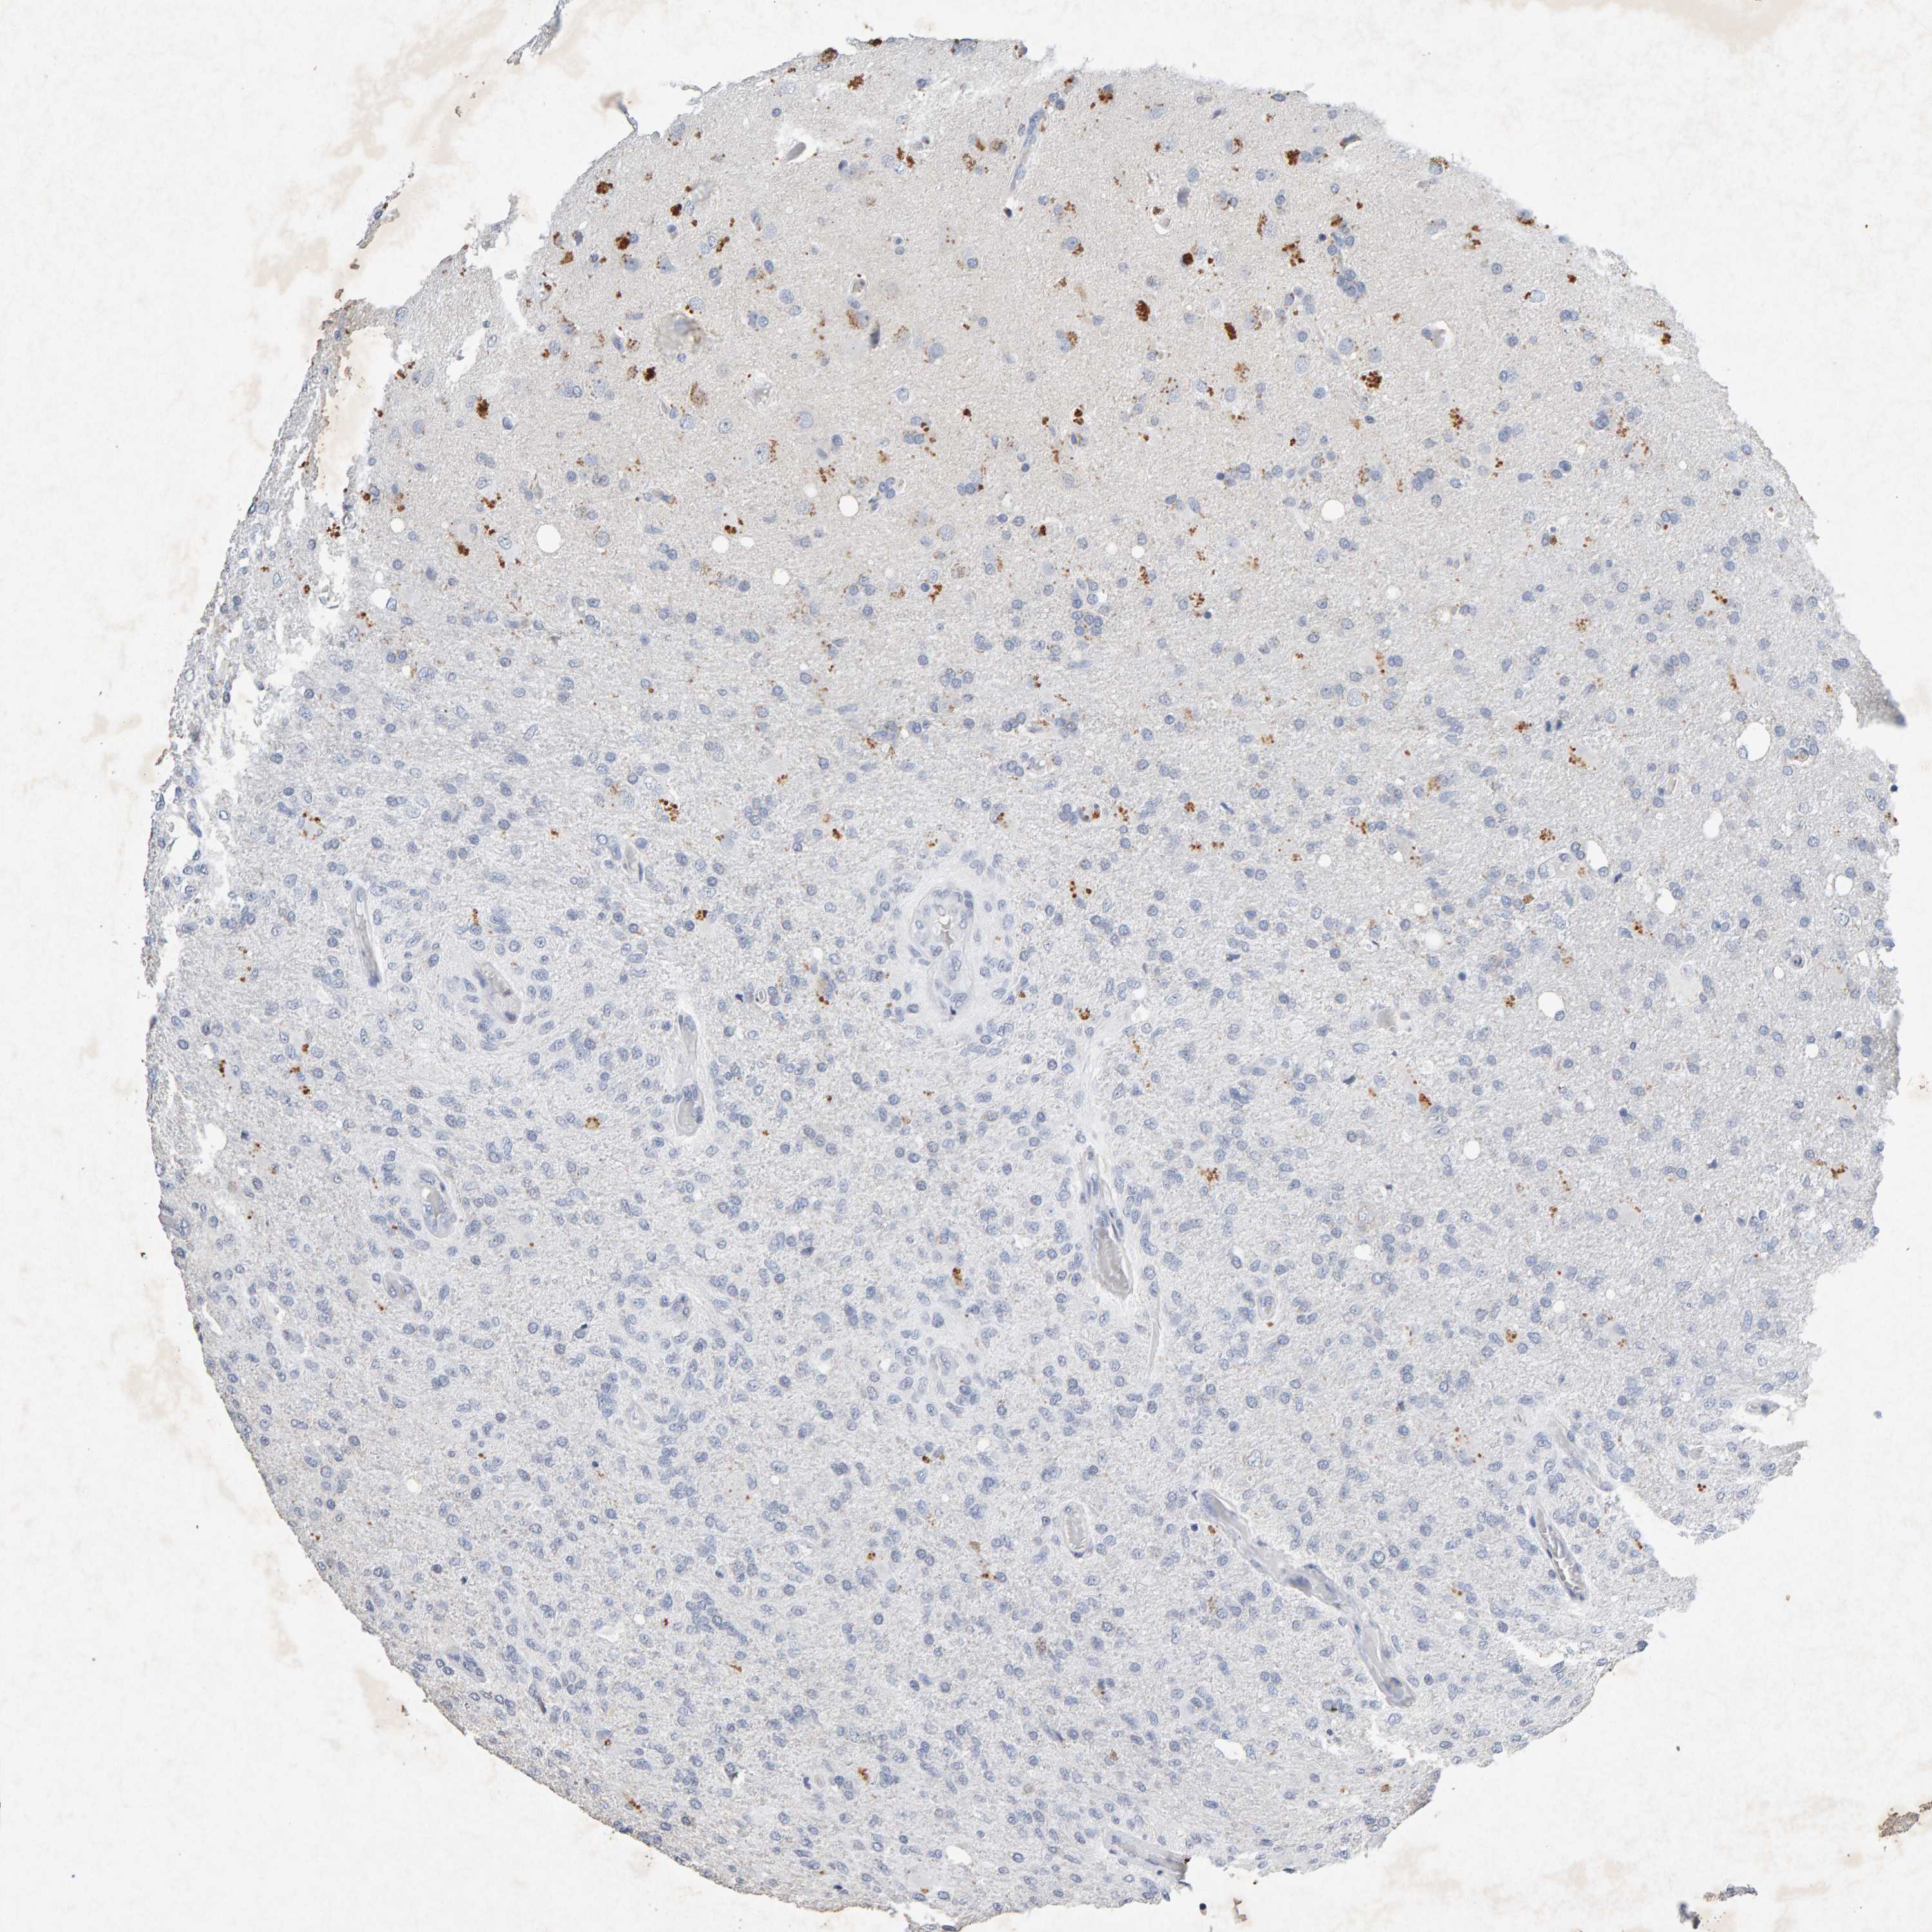

GLIOMA - Protein expressioni

A mouse-over function shows sample information and annotation data. Click on an image to view it in a full screen mode. Samples can be filtered based on level of antibody staining by selecting one or several of the following categories: high, medium, low and not detected. The assay and annotation is described here.

Note that samples used for immunohistochemistry by the Human Protein Atlas do not correspond to samples in the TCGA dataset.

Antibody stainingi

Antibody staining in the annotated cell types in the current human tissue is reported as not detected, low, medium, or high, based on conventional immunohistochemistry profiling in selected tissues. This score is based on the combination of the staining intensity and fraction of stained cells.

Each image is clickable and will lead to virtual microscopy that enables deeper exploration of all samples and also displays staining intensity scores, fraction scores and subcellular localization as well as patient and tissue information for each sample.

Antibody CAB022442

Antibody CAB022443

Staining

High

Medium

Low

Not detected

Intensity

Strong

Moderate

Weak

Negative

Quantity

>75%

75%-25%

<25%

None

Location

Nuclear

Cytoplasmic/membranous

Cytoplasmic/membranous,nuclear

Glioma, malignant, High grade

Glioma, malignant, Low grade